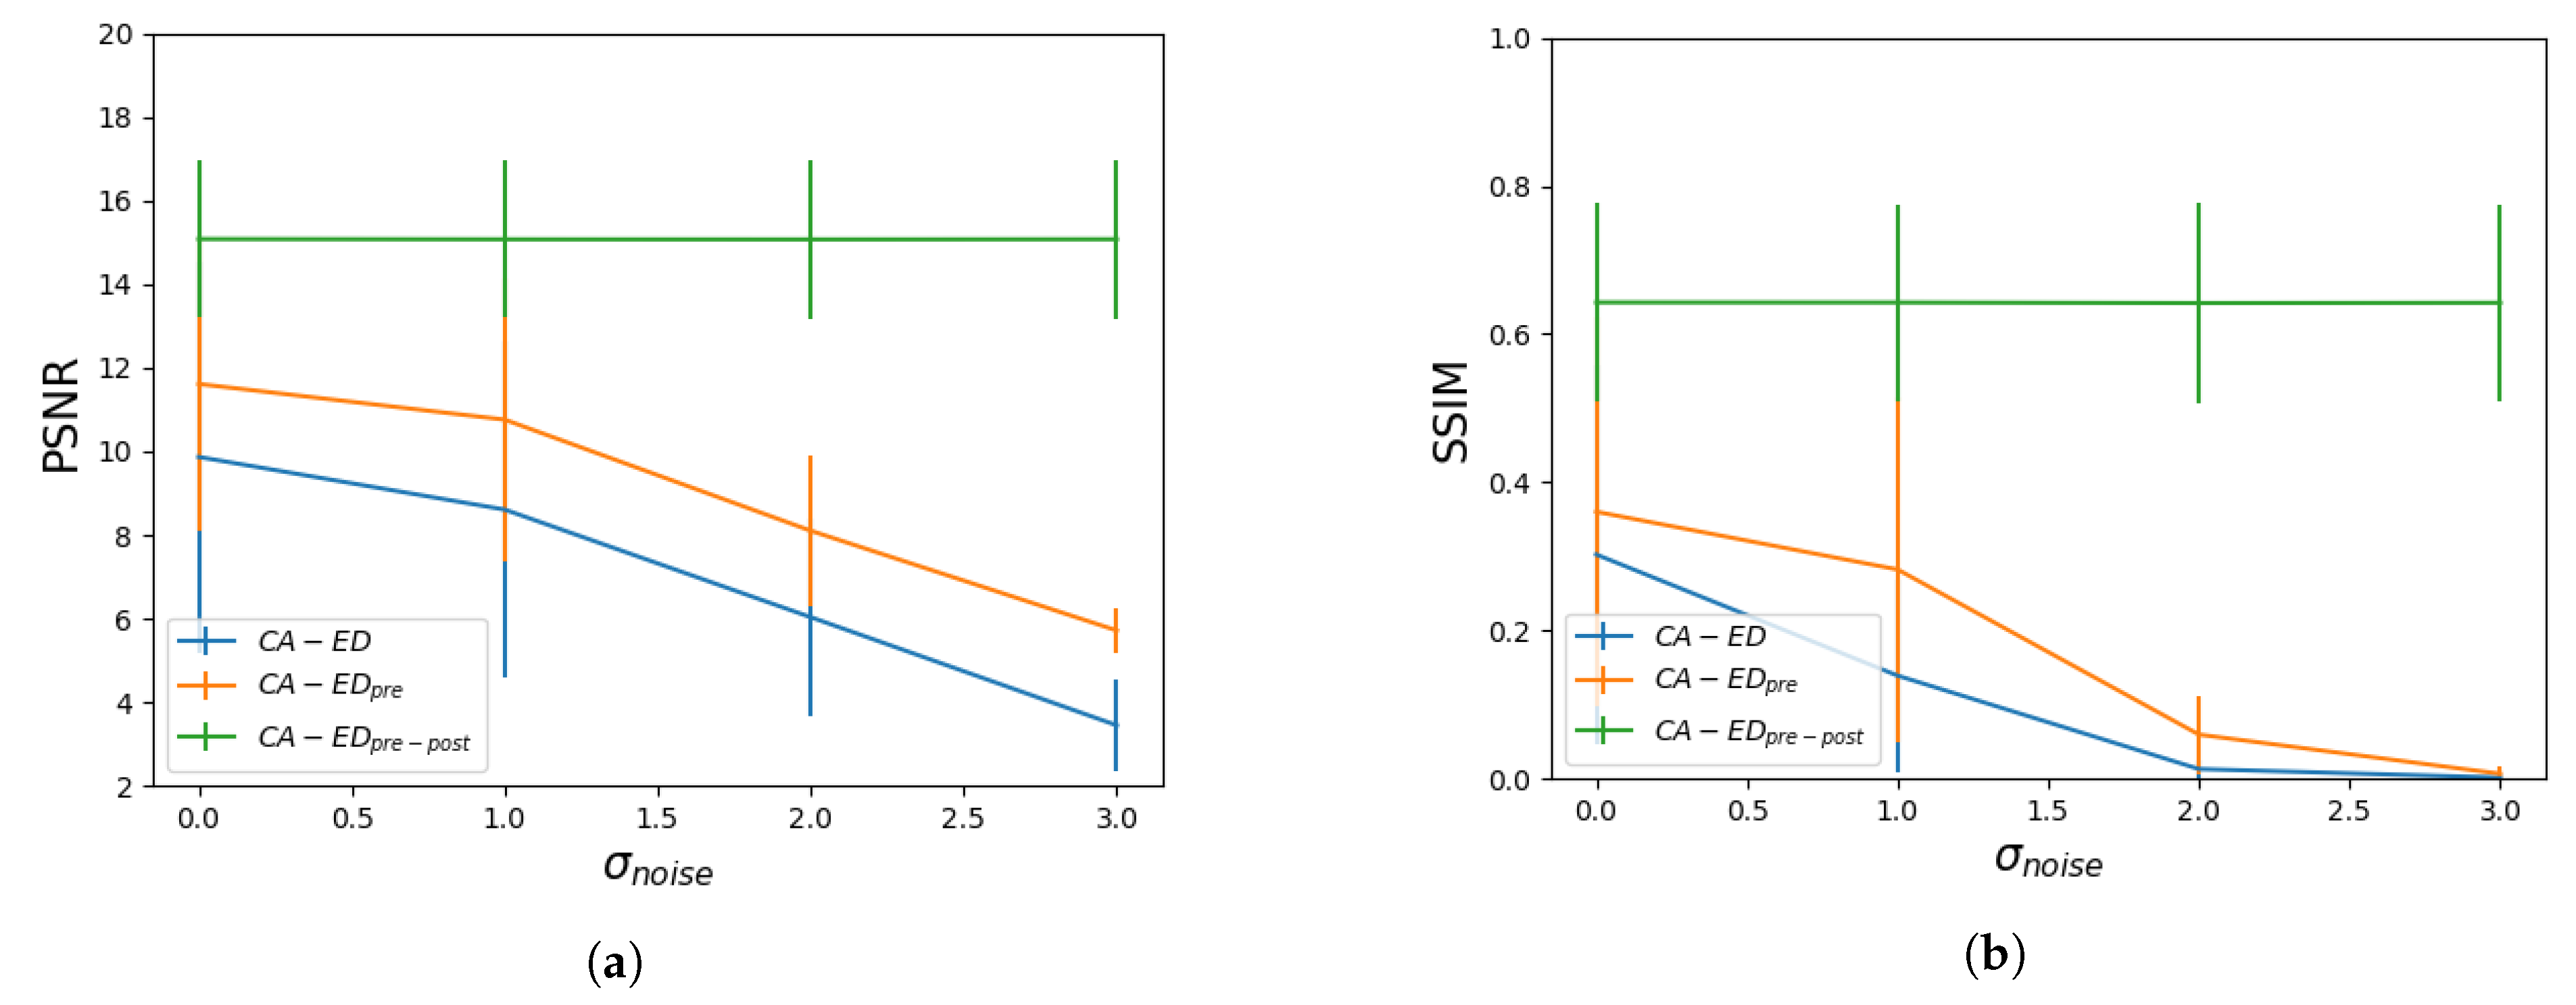

3.2. Robustness Analysis

3.2.1. Comparing , and

3.2.2. against the Canny Edge Detector

4.1. Robustness Analysis

4.1.1. Comparing , , and

4.1.2. against the Canny Edge Detector